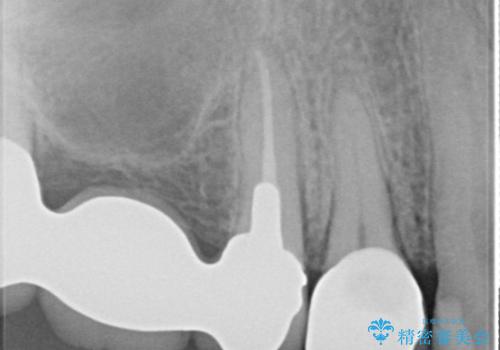

- 以前治療したセラミックインレーが破折したことを主訴に来院されました。

咬合力が強く、残存歯質が少ないためオールセラミッククラウンによる治療を行いました。

今回は白い材料での修復を希望されたため、欠けるリスクが高いセラミックインレーは避け、セラミッククラウンにて治療を行いました。